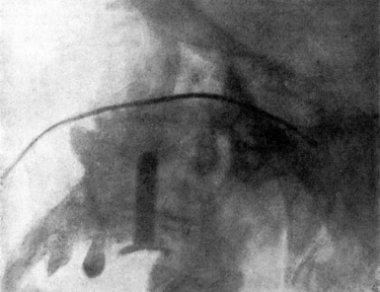

| 267. | Skiagram showing an Angular Tracheotomy Tube in the Trachea | 518 |

| 279. | Upper Bronchoscopy with the Patient in the Dorsal Position | 564 |

| 280. | Lower Bronchoscopy with the Patient in the Dorsal Position | 565 |